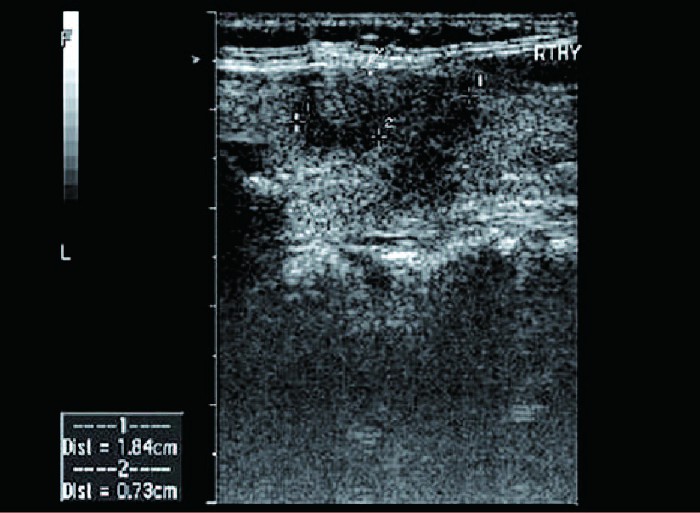

患者,女,34岁。因咽部干痛,右侧颈部肿大且有压痛感来院就诊。超声检查报告显示:甲状腺形态饱满,甲状腺左侧叶大小为5.6X1.5X1.3cm,右侧叶大小为5.7X1.9X2.0cm,峡部厚0.3cm。右侧叶表面欠光滑,实质回声减低,可见片状低回声区,边界欠清,左侧叶回声正常;双侧颈部探及多个淋巴结回声,大者约1.0×0.5cm,皮质增厚,CDFI:淋巴结内血流信号增多。

超声提示:亚急性甲状腺炎并颈部淋巴结肿大